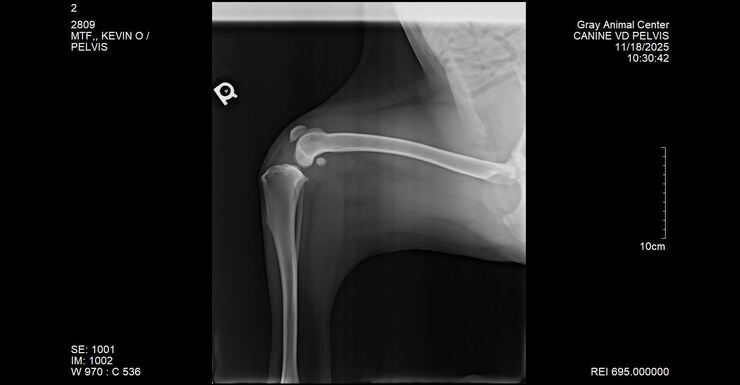

From the moment we walked him, we noticed he had an odd gait—stiff, limping, clearly uncomfortable. We asked for X-rays on the spot, and the shelter staff kindly accommodated. We sent those films to our vet here in Maine as well as had their vet review them. The news broke our hearts.

Kevin needed an FHO (femoral head osteotomy), a surgery where the head and neck of the femur are removed to relieve severe pain caused by a damaged or diseased hip. His injury likely happened long before he entered the shelter system back in January.

This week Kevin saw our vet for further assessment and new X-rays—and the news was devastating.

Kevin now needs a rear cruciate ligament repair and a luxating patella repair.

With Kevin weighing over 110 lbs, he is not a candidate for a simple lateral tie procedure. He will require metal plates, screws, and a very lengthy, restricted recovery. This dog cannot catch a break.